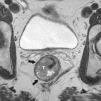

Grado de infiltración del tumorEn el diagnóstico por RM, cualquiera de las capas de la pared rectal se considera infiltrada en cualquier punto de su extensión cuando su intensidad de señal propia queda sustituida por la de la masa tumoral. Se describen varios estadios de infiltración según esta afecte a las diferentes capas del recto, mesorrecto u otras estructuras pélvicas. Un estadio T1 (fig. 2) implica la afectación de la mucosa y submucosa pero no así de la muscular, de manera que se conserva la hipointensidad de esta capa a lo largo de todo el anillo rectal, quedando la extensión del tumor por ella misma delimitada, sin ser invadida. Un estadio T2 (fig. 3) supone la afectación de la capa muscular, caso en el que su hipointensidad se pierde y se sustituye por la intensidad de señal del tumor, aunque conserva su contorno, sin infiltración en la grasa mesorrectal. Un estadio T3 (fig. 4) implica infiltración más allá de la muscular, por lo que el tumor se aprecia en la grasa como un frente redondeado o nodular3. La presencia de espiculaciones no es evidencia suficiente de infiltración3,4, ya que pueden estar causadas por fibrosis o por una inflamación peritumoral. Un estadio T4 (fig. 5) se da cuando la infiltración es de gran alcance y, rebasando la fascia mesorrectal, afecta a otras estructuras pélvicas, la hoja peritoneal (estadio T4a) o, una vez perforada esta, las vísceras intraperitoneales (estadio T4b).